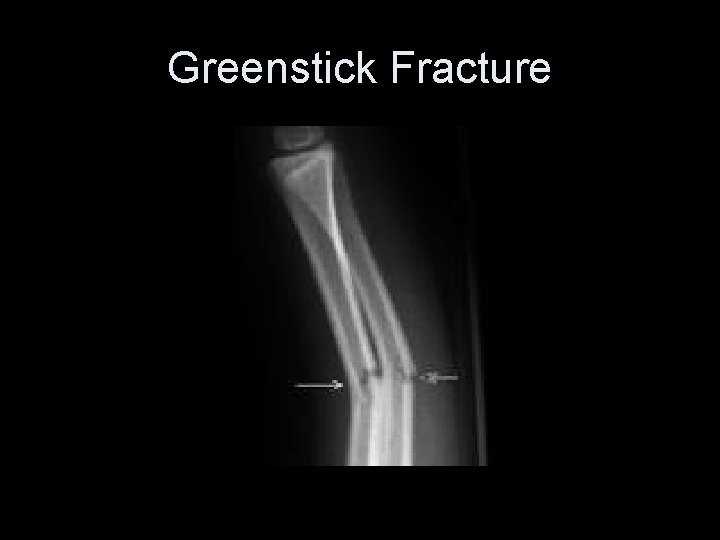

Incomplete Fracture 1. Part of bony structure gives way with little no displacement 1. Common example is a greenstick fracture 2. Torus fracture

Greenstick : Incomplete Fracture 1. Cortex breaks on one side without separation or breaking of the opposite cortex 2. Found almost exclusively in children under the age of 10

Greenstick Fracture